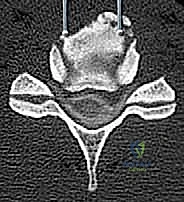

- التصوير بالرنين المغناطيسي (MRI): المعيار الذهبي لرؤية الحبل الشوكي، الأعصاب، والأقراص الغضروفية بوضوح تام، وتحديد مناطق الانضغاط.

- التصوير المقطعي المحوسب (CT Scan): ضروري جداً لتقييم البنية العظمية، التكلسات (مثل OPLL)، والكسور بدقة ثلاثية الأبعاد.

الخطوة 3: استئصال الأقراص الغضروفية وجسم الفقرة (Corpectomy)

باستخدام الميكروسكوب الجراحي وأدوات دقيقة جداً، يتم أولاً إزالة الأقراص الغضروفية أعلى وأسفل الفقرة المستهدفة. بعد ذلك، يتم استئصال جسم الفقرة العظمي المتضرر بعناية فائقة لفتح مساحة واسعة وتحرير الحبل الشوكي المضغوط.